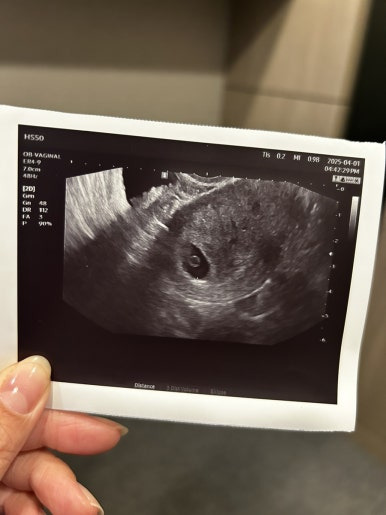

이 시기에만 볼 수 있다는 다이아몬드💍

화질이 엄청 선명하진 않지만

난황도 잘 커졌고, 그 위에 예쁘게 자리잡은 사탕이

사탕이는 그새 커서 0.37cm가 되었다👼🏻

(주기는 좀 밀려 5주로)